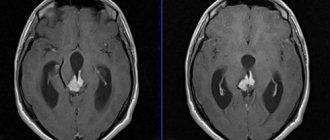

Очаги органического поражения мозга показаны стрелками

Анамнез позволяет определить продолжительность болезни, ее течение, связь с наследственностью. Неврологический осмотр является обязательным для выявления причин. Томография определяет атрофические очаги, которые и вызывают симптомы.